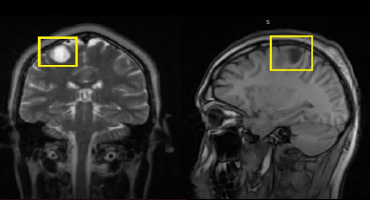

Resonancia Magnética

NEUROCISTICERCOSIS